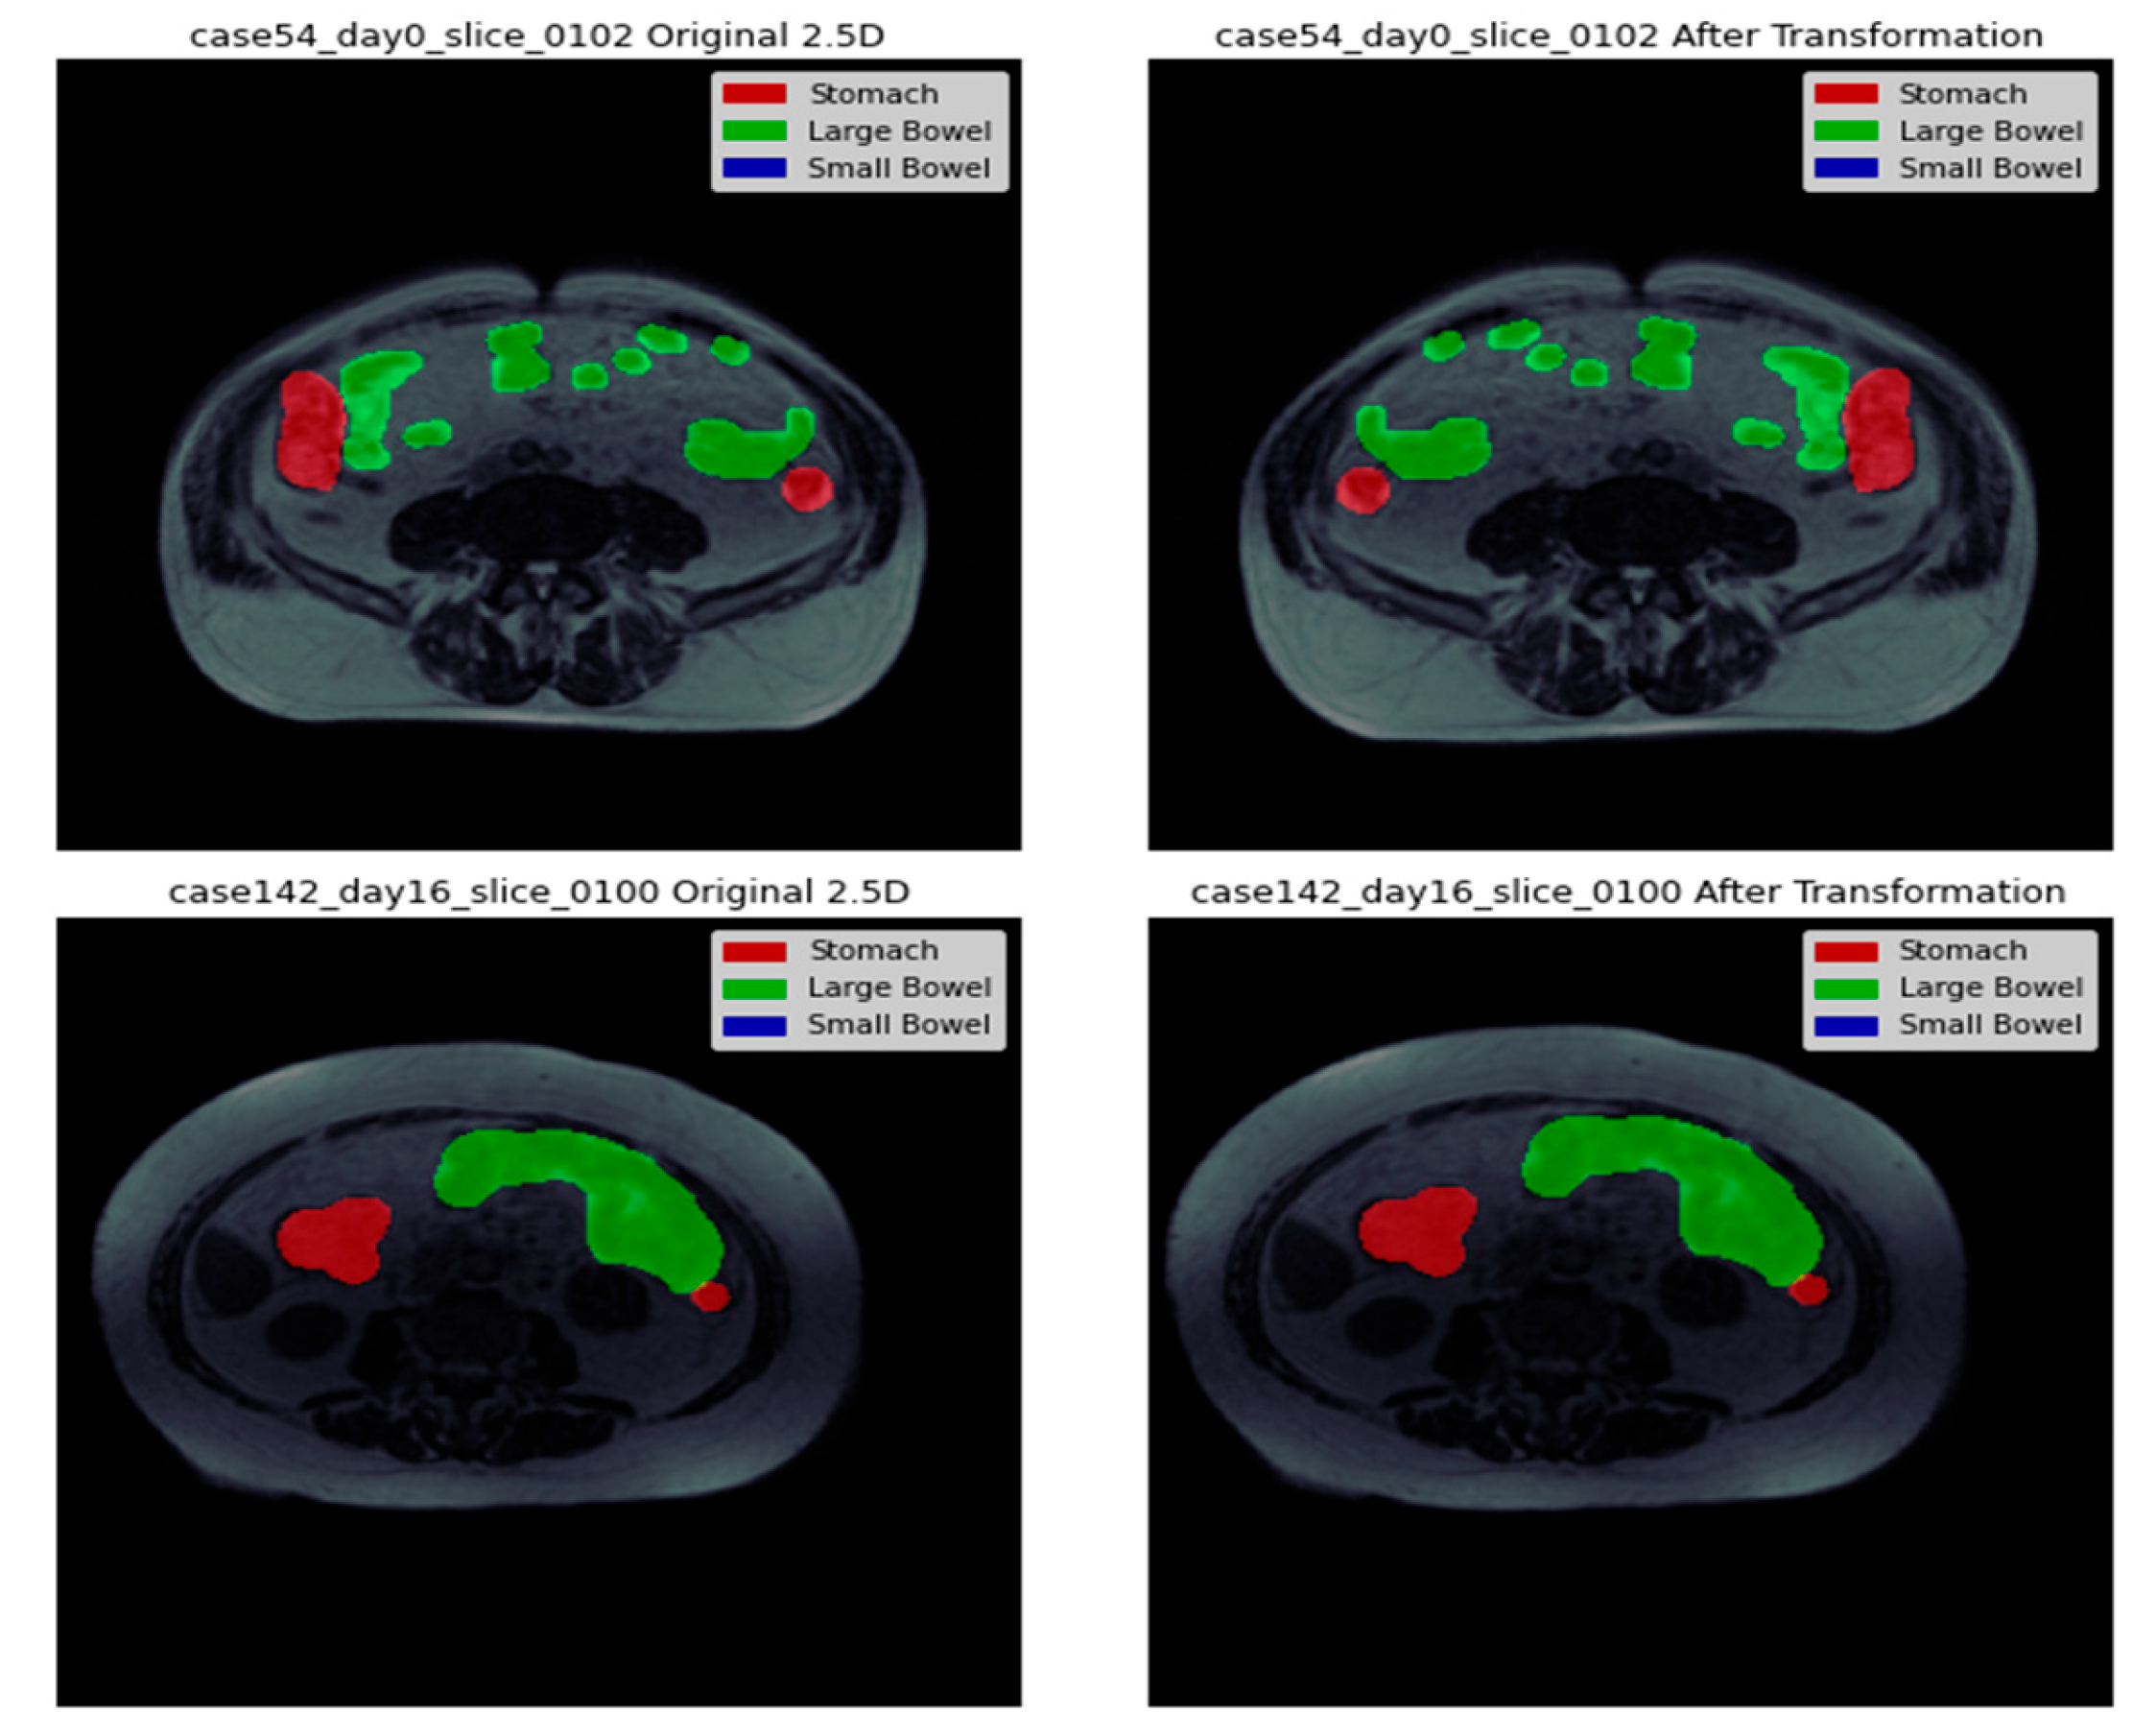

In our image processing pipeline, the next step in image preprocessing is embedding the mask information obtained from the metadata. The metadata contains details of organ segmentation based on pixel position and length. For each case ID, there can be three possibilities: no mask, all organs masked, or only some organs masked. Figure 3 presents a side-by-side representation of the images with their corresponding masks to provide a clear visualization of the segmentation process. The visual depiction shows that the separation between the stomach and large intestine decreases with each successive slice. This suggests a gradual decrease or less prominence of the stomach and large intestine regions in the images as we move through the slices. On the other hand, the segmentation of the small intestine shows a progressive increment with each consecutive slice. This indicates a growing prominence or clearer appearance of the small intestine region in the images as we progress through the slices.

Figure 3. Visual analysis of some images and masks.